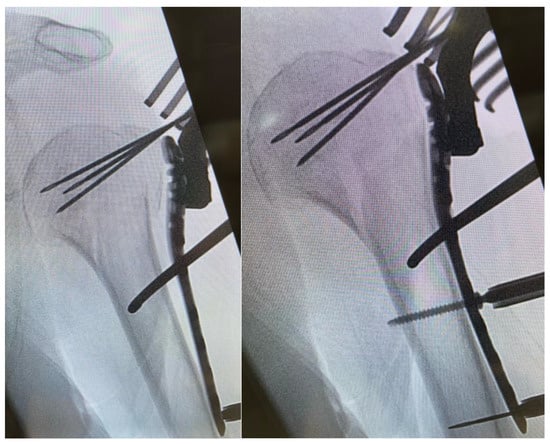

After a minimally invasive delta split procedure, traction sutures were applied through the rotator cuff. A reduction was achieved by the traction and manipulation of the sutures. In some cases, a reduction was achieved by the direct manipulation of the humeral head through the fracture. After a provisional fixation was achieved with 1.6 mm K-wires, the plate was placed and fixed with four to seven screws in the head and three screws in the diaphysis (Figure 2).

Figure 2. Plate placement, temporary fixation with K-wires and implantation of a cortex screw.